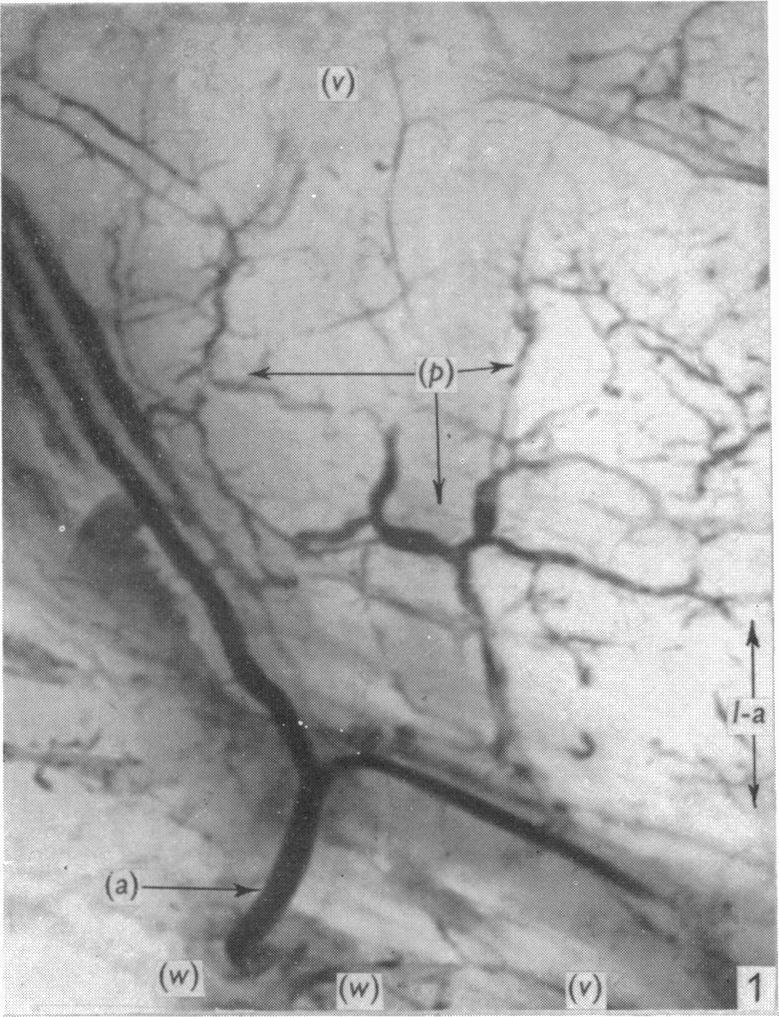

An x-ray microscopic study of the postnatal development of the vasa vasorum in the human aorta.

J Anat. 1965 Oct;99(Pt 4):877-89.

An x-ray microscopic study of the postnatal development of the vasa vasorum in the human aorta.人体主动脉中血管滋养管产后发育的X射线显微镜研究。